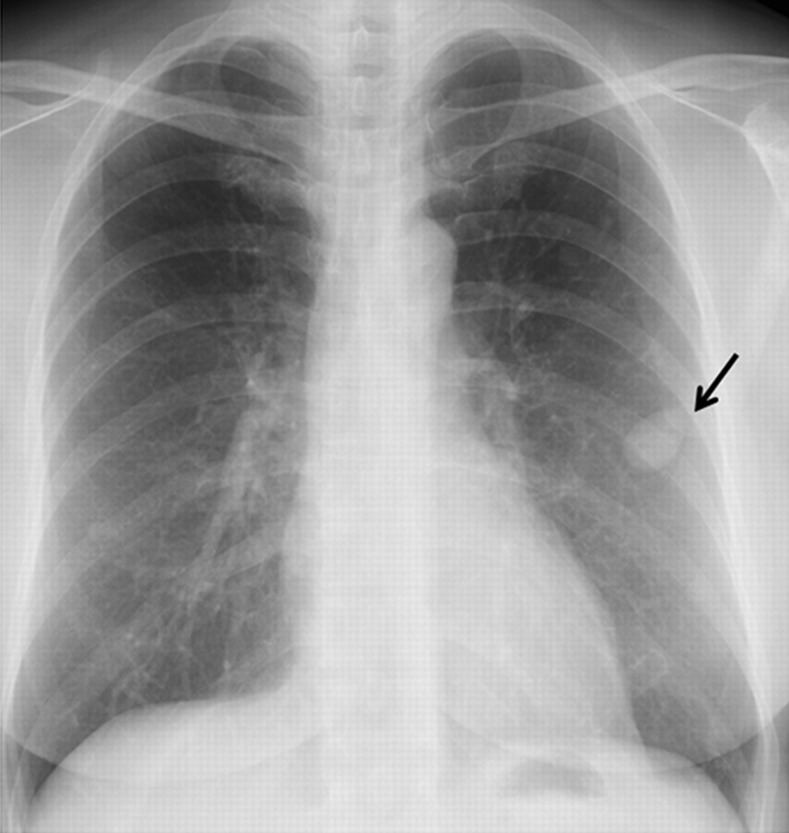

We report a case of multiple benign metastasizing leiomyoma (BML) lung nodules showing faint or non-avid uptake of F-18 fluorodeoxyglucose (FDG) (respective 1-hour early and 2-hour delayed maximum standardized uptake values; 1.3 or less and 1.2 or less) in a 50-year-old woman with a history of hysterectomy for uterine leiomyoma at the age of 38 years. When multiple lung nodules show faint or non-avid FDG uptake in a patient with a history of hysterectomy for uterine leiomyoma, BML should be included in the differential diagnosis.